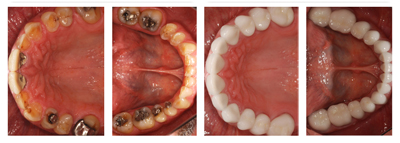

Top Class Treatment

All Types Dental Services